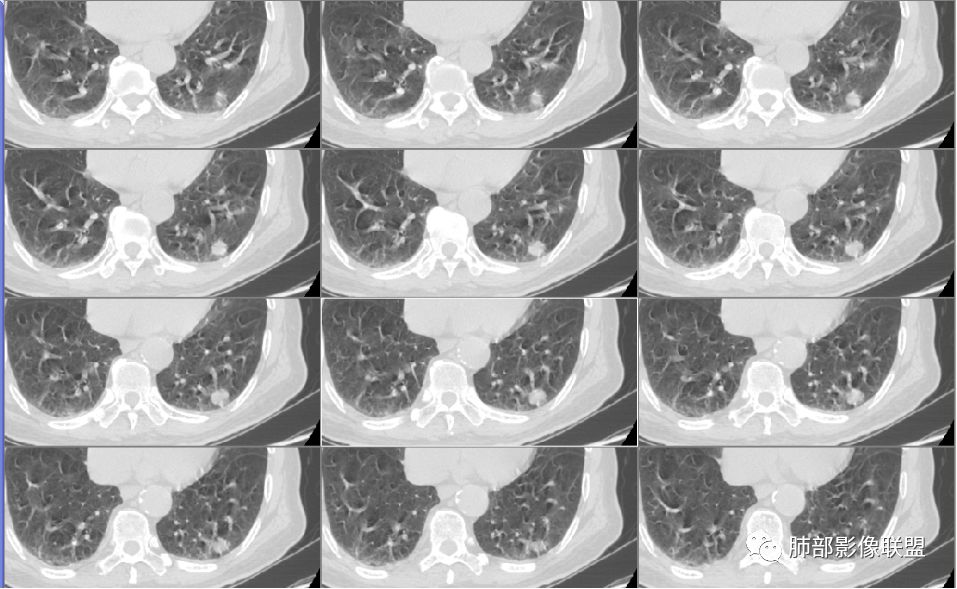

应当说两例患者影像学表现都具有比较明显恶性征象,中老年男性患者,均都没有呼吸系统临床症状。

病例1为胸膜下实性小结节,血管脐凹样出入,可见支气管阻塞。病灶膨隆,部分边缘平直,周围晕征不明显,未见分叶,但可见毛刺及胸膜牵拉,增强后明显强化,老年男性,怀疑新生物尤其是腺癌是有理由的。